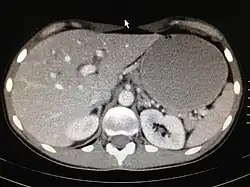

Die ergiebigste Untersuchungsmethode des Magens ist die Gastroskopie (Magenspiegelung). Bei der Magenspiegelung wird oft ein HU-Test zum Nachweis einer Helicobacter-Besiedlung entnommen. Außerdem sind gezielte Biopsien zur histologischen Untersuchung leicht möglich. Die Röntgenuntersuchung des Magens, die vor dem Aufkommen der Gastroskopie betrieben wurde, wird heute nicht mehr routinemäßig durchgeführt, da sie sehr unsichere Ergebnisse produziert. Die Ultraschalluntersuchung des Magens ist leicht möglich, liefert aber nur selten brauchbare Ergebnisse, wie zum Beispiel eine Magenausgangsstenose oder eine auffällige irreguläre Wandverdickung. Beim Ultraschall ist der Magenausgang recht gut, andere Teile wie z. B. die Cardia kaum beurteilbar. Eine Computertomographie des Magens ist ebenfalls nur in Ausnahmefällen sinnvoll. Zur Bestimmung von Helicobacter-Bakterien wird zunehmend ein Atemgastest durchgeführt.